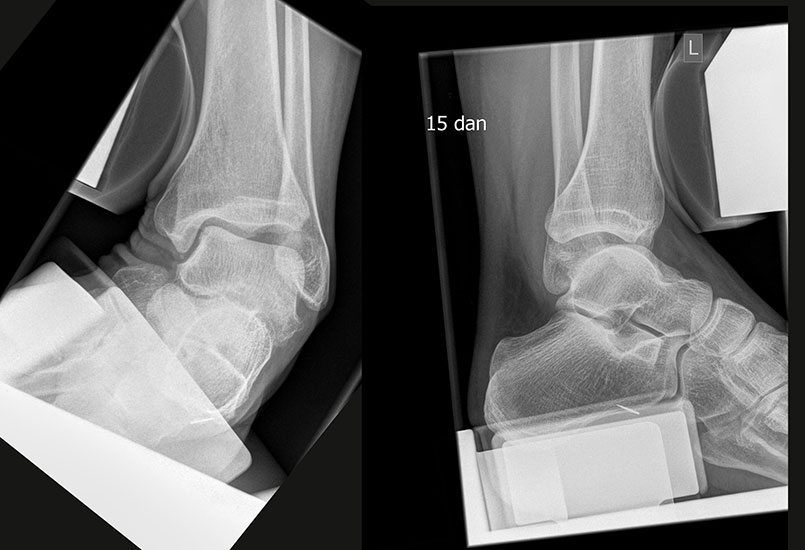

Röntgenaufnahmen dienen vor allem zum Ausschluss einer knöchernen Verletzung und umfassen Aufnahmen des Sprunggelenks anterior-posterior, lateral und 20° Innenrotation (Mortise view). Die über viele Jahre empfohlenen gehaltenen Aufnahmen haben ihre Bedeutung bei der Akutverletzung vollständig verloren, da sie die Behandlungsstrategie nicht beeinflussen (Abb. 2). Bei einer chronischen Instabilität liefen gehaltene Aufnahmen zusätzliche Informationen, wobei auch hier falsch negative Befunde möglich sind 26. Die höchste Zuverlässigkeit liefert die dynamische Untersuchung in Narkose 27